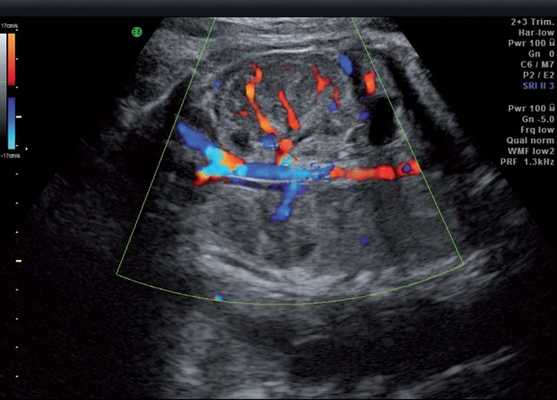

Лоханка правой почки была расширена до 13 мм, паренхима истончена и гиперэхогенна, кортикомедуллярная дифференцировка отсутствовала. При ЦДК кровоток в паренхиме не визуализировался. Вокруг правой почки по всему ее периметру определялось анэхогенное образование размером 56×20×26 мм (рис. 1, 2). Мочеточники с обеих сторон не визуализировались. Изменения левой почки отсутствовали. Мочевой пузырь был удовлетворительного наполнения и опорожнения. Оба надпочечника визуализировались.

Рис. 2. Истончение паренхимы правой почки плода с отсутствием кровотока в режиме ЦДК.